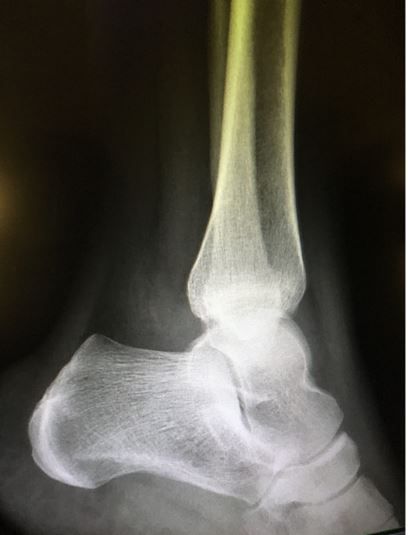

A 32-year-old woman is seen in the ED with pain from an ankle injury sustained about 24 hours earlier. What does the x-ray show? How would you proceed?

Initial diagnostic testing. Ankle x-ray (below)